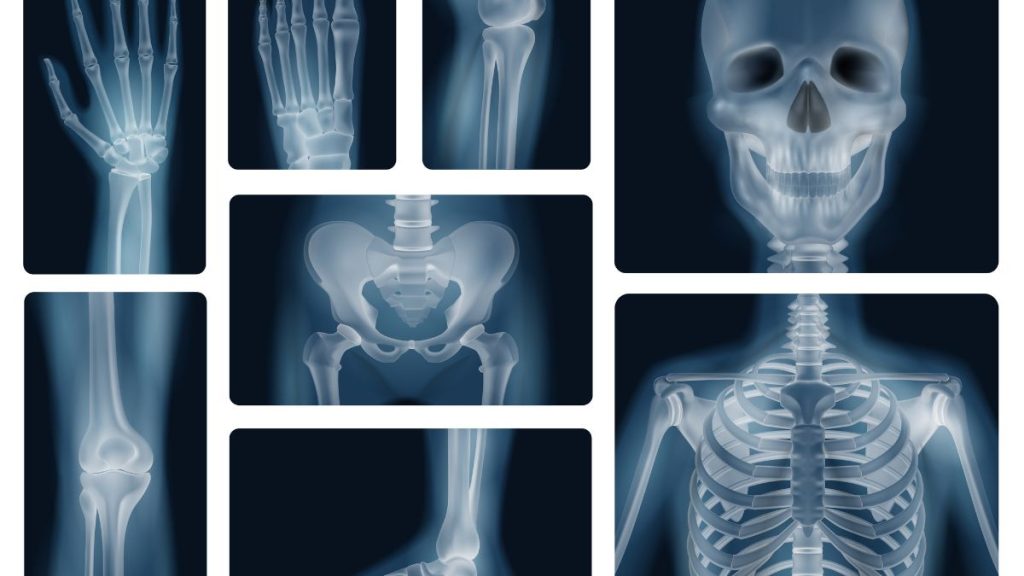

Os estudos radiográficos mantêm importância na avaliação de patologia torácica (pneumonia, pneumotórax, complicações da prematuridade, malformações congénitas) e osteoarticular (idade óssea, fraturas, displasias e doenças metabólicas). As radiografias abdominais são úteis na suspeita de oclusão intestinal ou enterocolite necrotizante, sobretudo em recém-nascidos prematuros. Os exames contrastados sob fluoroscopia continuam relevantes na avaliação de má-rotação intestinal, oclusão intestinal neonatal e fístulas traqueoesofágicas.